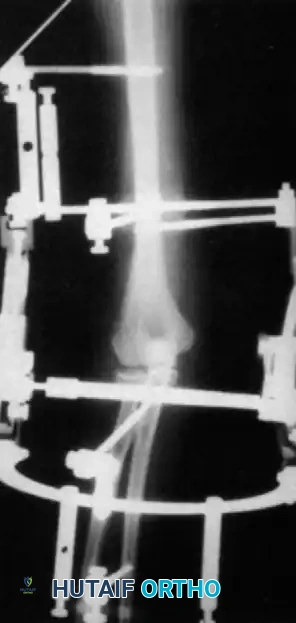

Hinged External Fixation

The current gold standard for managing instability following extensive open reduction is the application of a hinged elbow external fixator. Jupiter, Ring, and Hotchkiss have demonstrated excellent results using hinged fixators to maintain concentric joint reduction, permit early active/passive motion, and enhance muscle-tendon stretching.

Fig. 58-25 Late-discovered medial elbow dislocation managed with open reduction and hinged external fixation without primary ligament repair. (From Hotchkiss RN: Fractures and dislocations of the elbow, 1996.)